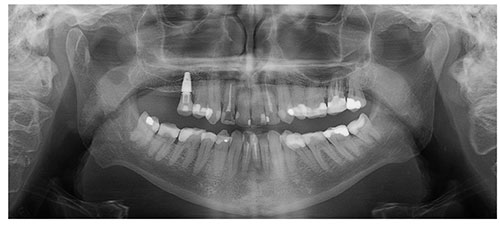

3Dセンサーを使用した2D撮影

当社の高度なSmartPan™ イメージングシステムは、2D撮影にも同一の3Dセンサーを使用するため、CBCTとパノラマ撮影を切り替える際にセンサーを変更する必要がありません。複数のパノラマ画像から診断に最適な画像を選択できます。